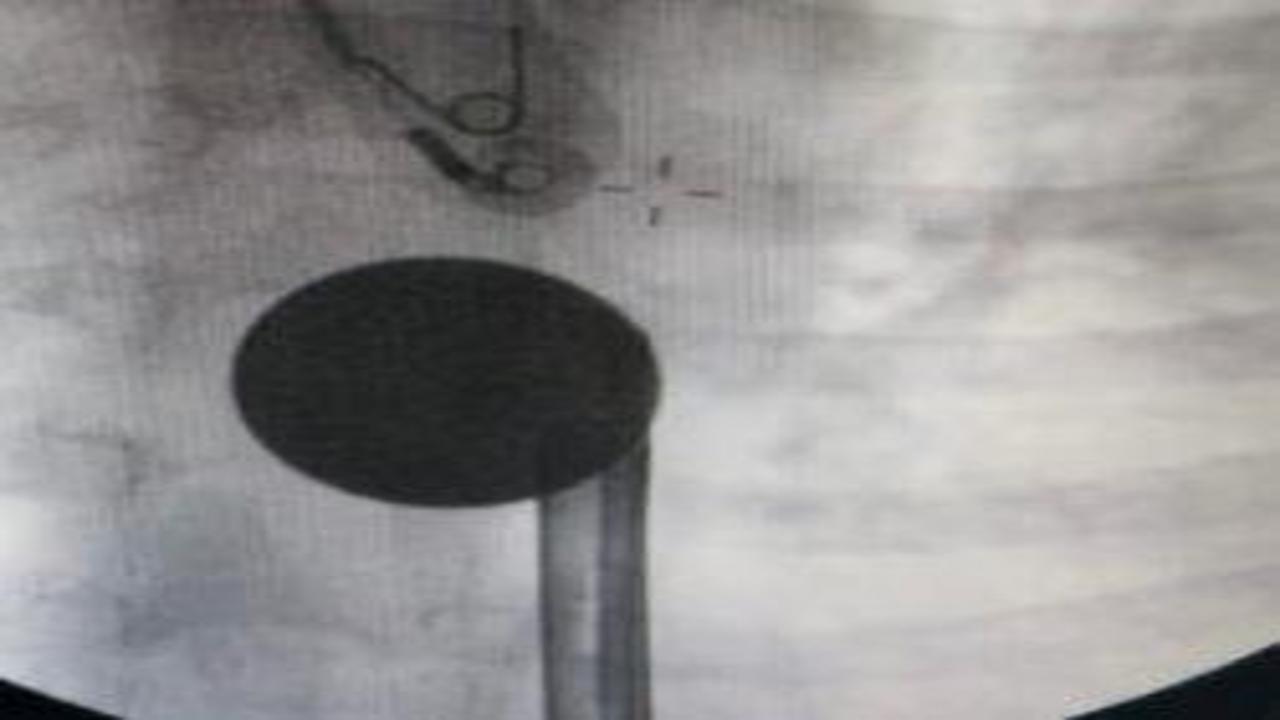

Siirt'te 8 yaşındaki çocuğun boğazına madeni 5 lira kaçtı. Hastaneye götürülen çocuğu doktorların titiz çalışması kurtardı.